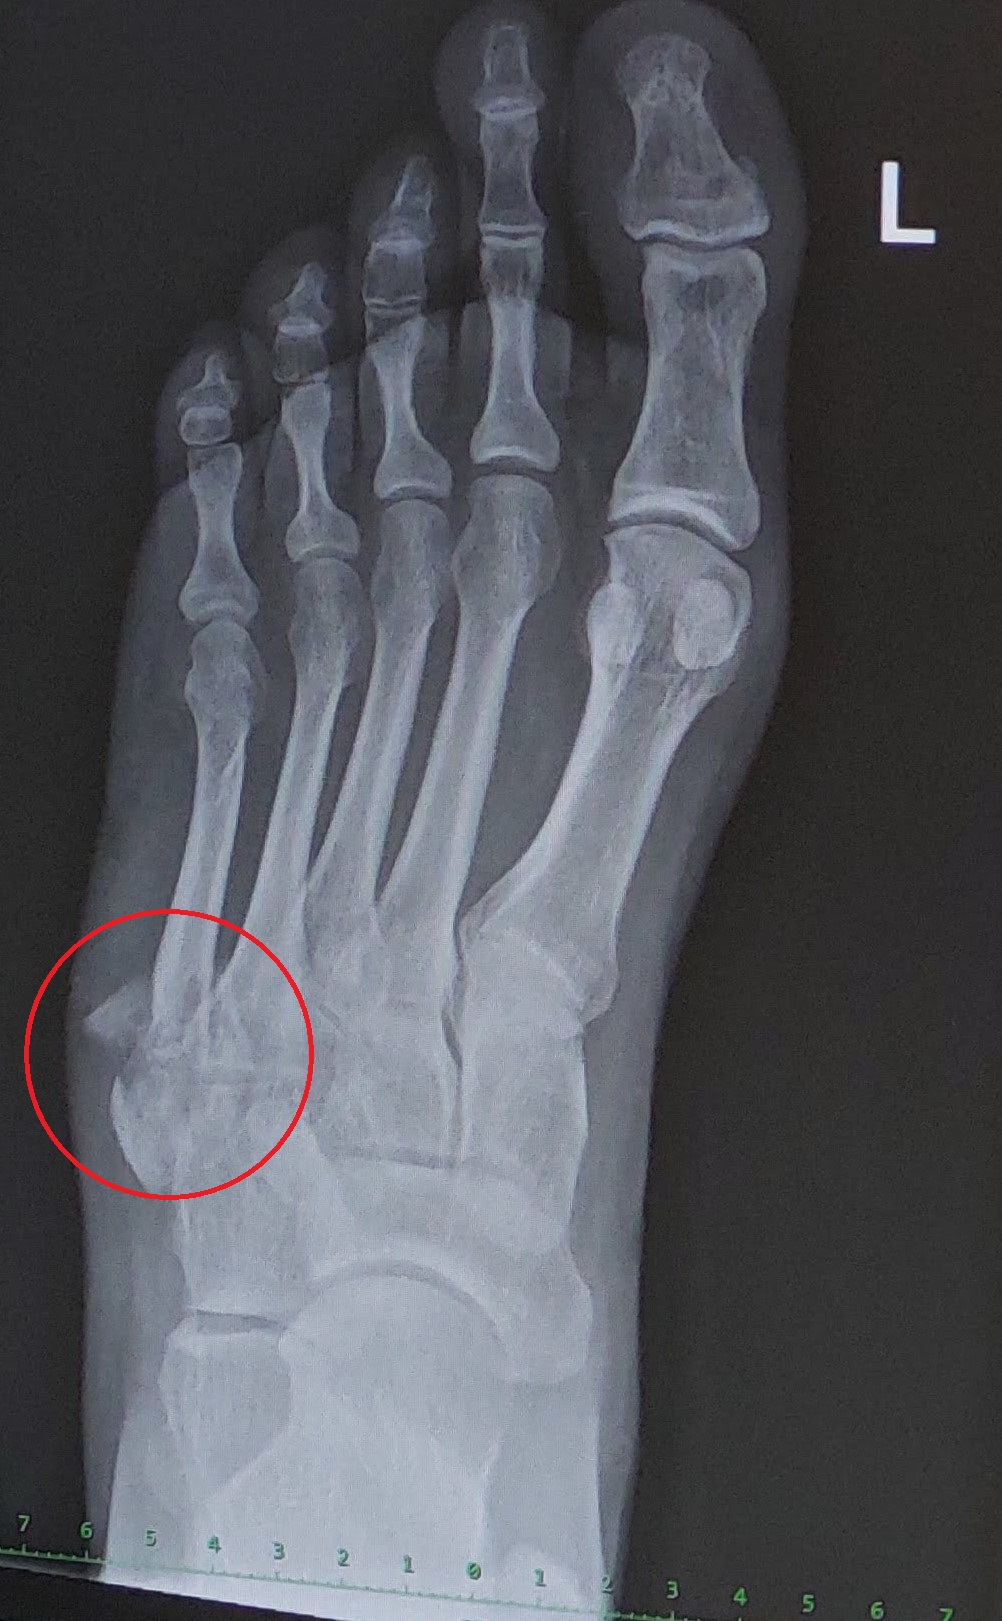

pred 14 dny zlomenina kosti malikove hrany na noze - praskly zebrik je previt. prikladam kontrolni rtg. hoji se to vyborne. mel jsem i rozseklou nohu a par stehu. taky se hoji dobre. bolestivost ustoupila. otok se zlepsil. drobny problem je ulomek kosti ktery tam trci - viz prilozeny snimek.

rad bych sel cestou kdy se kost remodeluje a ustepek se "zpracuje-srovna-rozpusti" sam misto dalsiho rezani a vystipnuti ulomku.

beru D3 a K2 a C, kolagen, Becka, horcik, vapnik, orechy, aspirin...

napada vas jeste neco dalsiho jak tomu pomoc aby bylo rozpusteni a srovnani ulomku mozne a rychle?

20230828_114616.jpg

20230828_114616.jpg [ 375.45 KiB | Zobrazeno 9875 krát ]